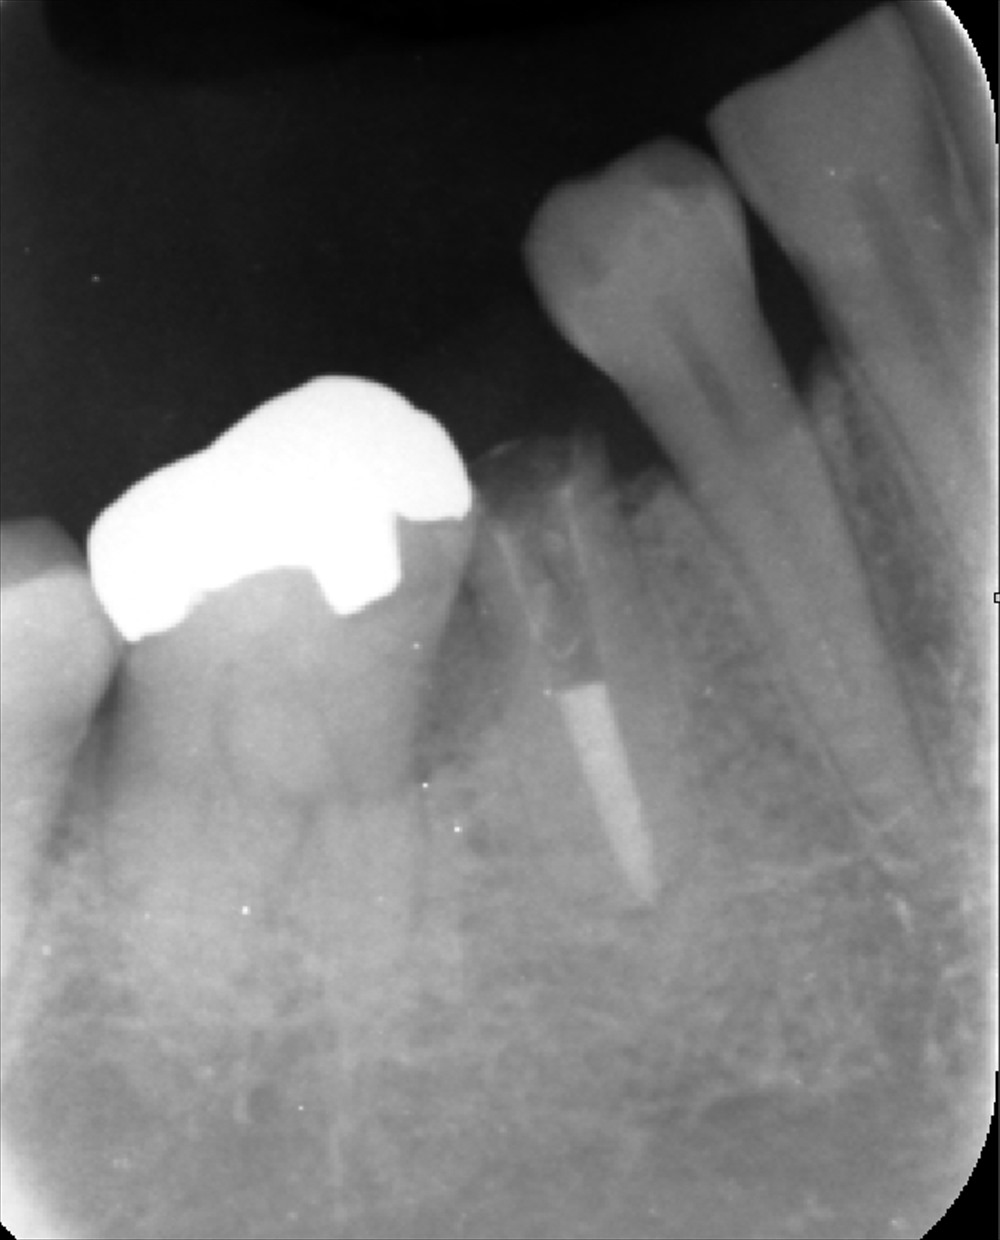

次のケースは今日で3回目の精密根管治療

綺麗になりました。症状もなくOK!!

ラストスパート

最終的なお薬を入れます。レーザー

よっこいしょ

術前

術後

次回から土台へGO!!